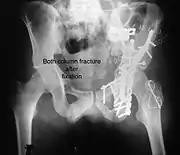

Posterior column and wall fixed using screws and plates

Both column fracture after fixation with screws and plates

The final management depends on the size of the fragment(s), stability and congruence of the joint. In some cases traction for six to eight weeks may be the only treatment required; however, surgical fixation using screw(s) and plate(s) may be required if the injury is more complex. The latter treatment will be called for if bone fragments do not fall into place, or if they are found in the joint, or if the joint itself is unstable.